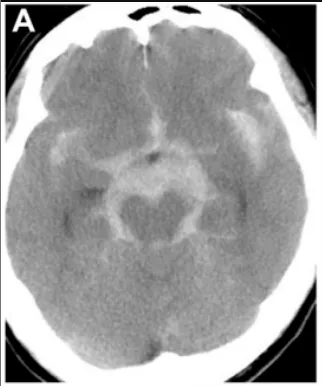

47岁男性患者陈先生在家中出现突发性剧烈头痛,随后迅速陷入昏迷状态。家属紧急送医后,急诊CT检查显示弥漫性蛛网膜下腔出血,左侧脑桥前池增厚表现明显。

出血后第18天,患者病情稳定后,医疗团队实施脑血管造影检查。检查结果揭示左侧大脑后动脉P1-P2段存在异常扩张伴狭窄表现——符合夹层动脉瘤的典型影像学特征。